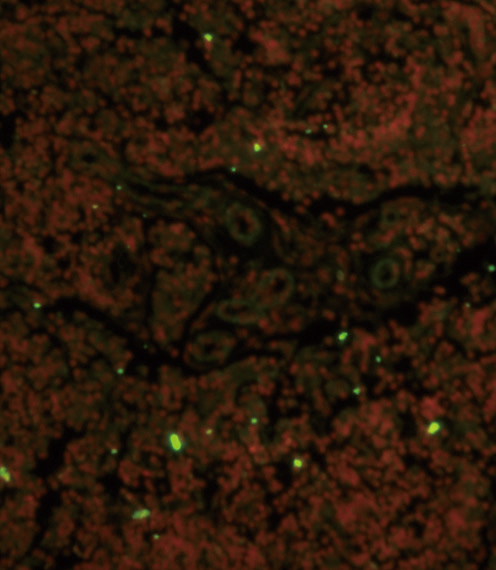

![FACS analysis of human peripheral blood lymphocytes using GTX01455-08 CD19 antibody [HIB19] (PE). Solid lone : primary antibody Dashed line : isotype control antibody amount : 0.25 μg (5 μl)](https://www.genetex.com/upload/website/prouct_img/normal/GTX01455-08/GTX01455-08_20200428_FACS100_w_23053121_847.webp)